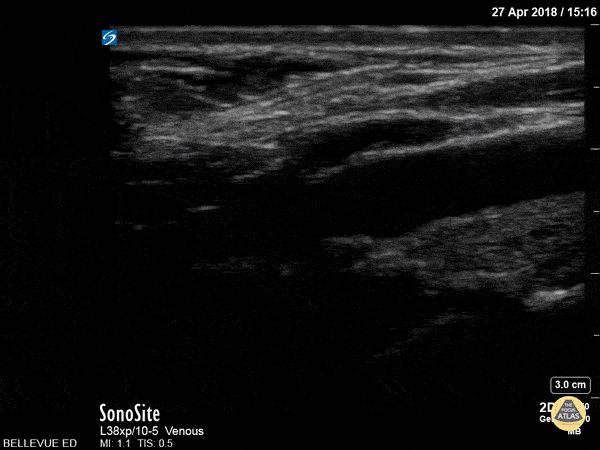

Vascular - Carotid Bulb Long Axis

The pulsatile carotid artery in long axis at the level of the carotid bulb (widened segment in center of the screen). The intima is visible as a distinct layer of the carotid wall. The bifurcation of the internal and external carotid is not visible here. A portion of the internal jugular vein is seen superficial to the carotid. Hannah Kopinksi and Dr. Lindsay Davis - NYU Emergency Medicine